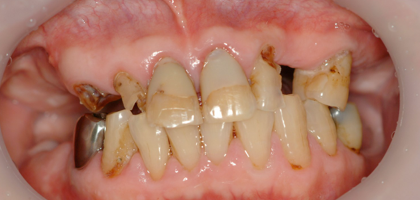

一日も歯がないという状態はありません。 この写真の方も前歯しか残っていませんが、インプラント手術当日まで前歯は残しておいて、その当日に抜歯、インプラントを入れて仮歯を固定しています。つまり、歯は一日で入るので、歯が無い、見た目が悪いという状態は全くありませんので、ご心配なく。大分県大分市スマイルライン歯科ではオールオンフォー(all- on- 4)の治療を全国でもいち早く行い数多くの症例を手掛けてきました。そして治療を行ったすべての患者様に喜んで頂いておりますのでご希望の方はまず、CTレントゲンなどで骨の形を診査しますのでお問い合わせください。

前歯しかない患者様で前歯がないと見た目が困るということでお越しになりました